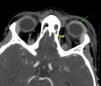

En los estudios de laboratorio destacan proteína C reactiva 331mg/L, procalcitonina 105,5 ng/mL, gammaglutamil transpeptidasa 159 UI/L, sodio 127 mEq/L y cloro 96 mEq/L, con aumento de fibrinógeno (665mg/dL). En el hemograma: leucocitosis (21,6×10e9/L), con desviación izquierda (neutrofilia 90%). Se realiza una TC craneal con contraste, evidenciando colección subperióstica en el margen nasal de la órbita izquierda y en el tejido celular subcutáneo de 17×8mm con realce periférico. Trombosis de la vena angular izquierda, con extensión a la vena orbitaria superior que no alcanza el seno cavernoso, con ingurgitación de los vasos conjuntivales relacionada con la trombosis. Ocupación de senos frontales, maxilares y esfenoidal derecho y parcial de celdillas etmoidales y mastoideas (figs. 2 y 3).